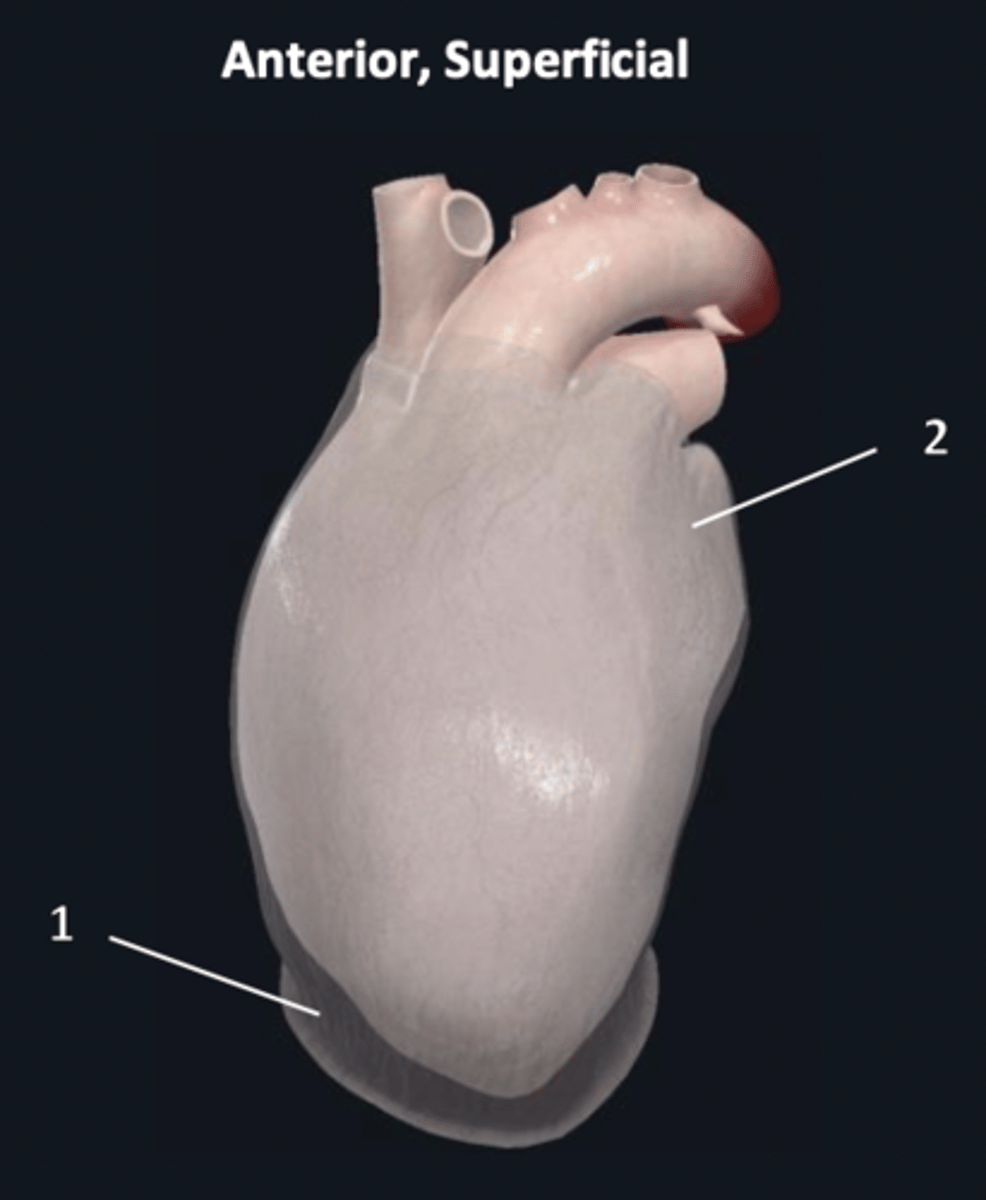

fibrous pericardium

1 (superficial)

parietal layer

2 (deep to 1)

apex

1

base

2